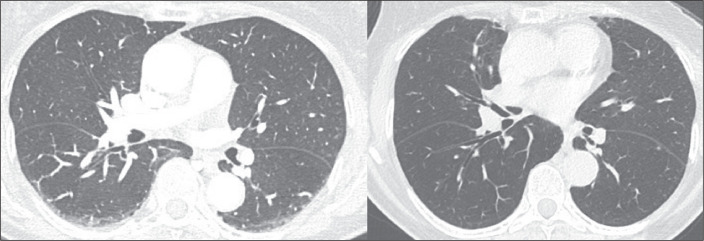

Objective: To conduct a survey on the use of the term "interstitial lung abnormalities" in radiology reports in Brazil, propose an appropriate Portuguese-language translation for the term, and provide a brief review of the literature on the topic.

Results: A total of 163 responses were received, from all regions of Brazil. Although the vast majority (88%) of the respondents stated that they were familiar with the term "interstitial lung abnormalities", there was considerable variation regarding the equivalent term they used in Portuguese.

Conclusion: We suggest that the term "anormalidades pulmonares intersticiais" be used in order to standardize radiology reports and disseminate knowledge of these findings in Brazil.